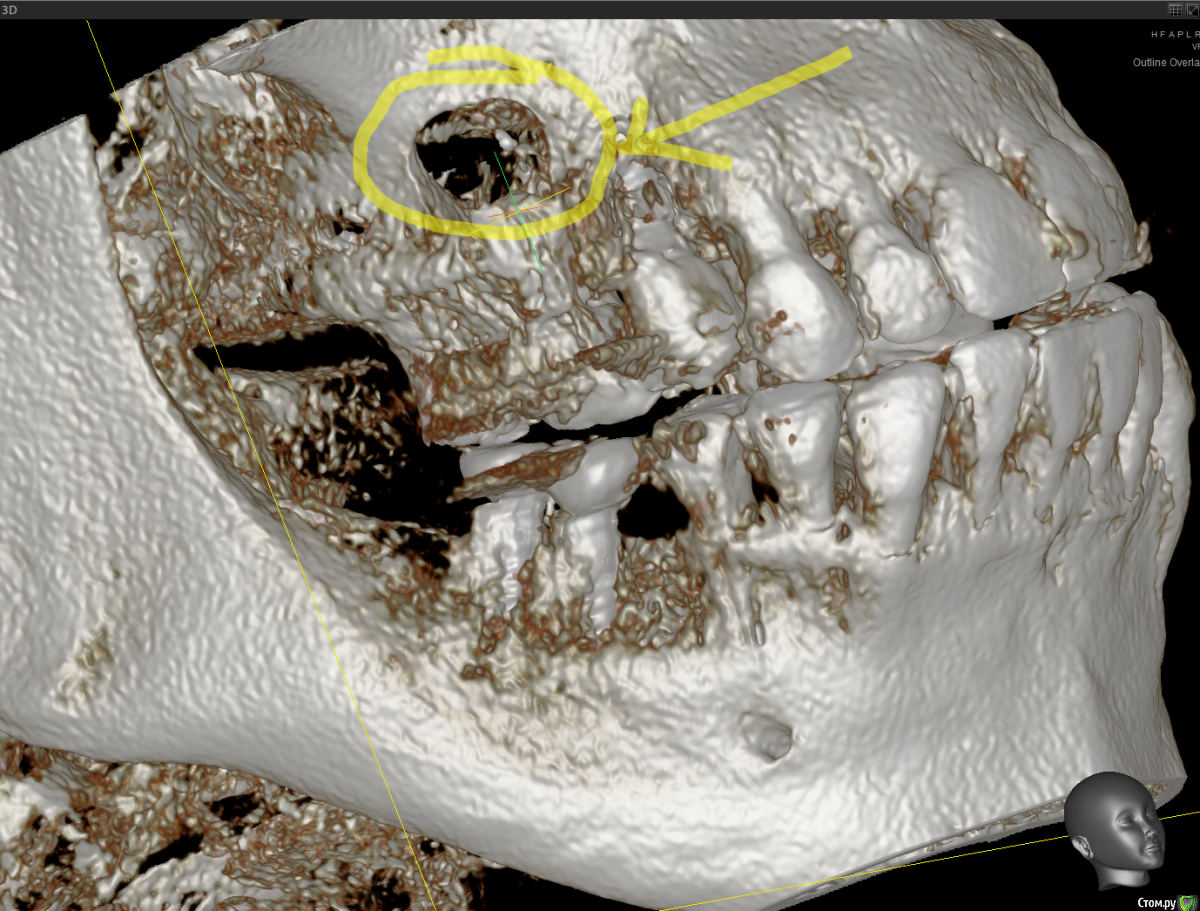

Raystom Опубликовано 20 февраля, 2021 Поделиться Опубликовано 20 февраля, 2021 Обратилась пациентка с неприятными ощущениями в области зубов 26, 27, во рту эти зубы показались мне темнее остальных, на КТ видна вот такая красота. Каков план лечения в таких ситуациях? Попробовать отделить пазуху от грануляций или просто удалить и после лечения ЛОРа идти на закрытие ОАС? Как после восстанавливать кость? И какие временные промежутки. Понимаю, что многие скажут при таких вопросах передать другим, но это не мой вариант. Мб есть литература по подобным случаям? Ссылка на комментарий

колесников Опубликовано 25 февраля, 2021 Поделиться Опубликовано 25 февраля, 2021 Киста сделала синуслифтинг,этот объём надо сохранить,колапол резорбируется быстро и через 3-6 мес останется 3мм,графт не скиснет,а созреет по форме дефекта,надо избежать вторичного инфицирования. Перекрыть вестибулярным лоскутом лунку не получится,раскрытие-инфицирование,боль,отёк,контрактура,смешение биотипа. Зачем? Можно нёбный мобилизовать или выбрать другой способ герметичного закрытия лунки Ссылка на комментарий

Raystom Опубликовано 25 февраля, 2021 Автор Поделиться Опубликовано 25 февраля, 2021 Киста сделала синуслифтинг,этот объём надо сохранить,колапол резорбируется быстро и через 3-6 мес останется 3мм,графт не скиснет,а созреет по форме дефекта,надо избежать вторичного инфицирования. Перекрыть вестибулярным лоскутом лунку не получится,раскрытие-инфицирование,боль,отёк,контрактура,смешение биотипа. Зачем? Можно нёбный мобилизовать или выбрать другой способ герметичного закрытия лункиПонятно, спасибо, буду делать Ссылка на комментарий